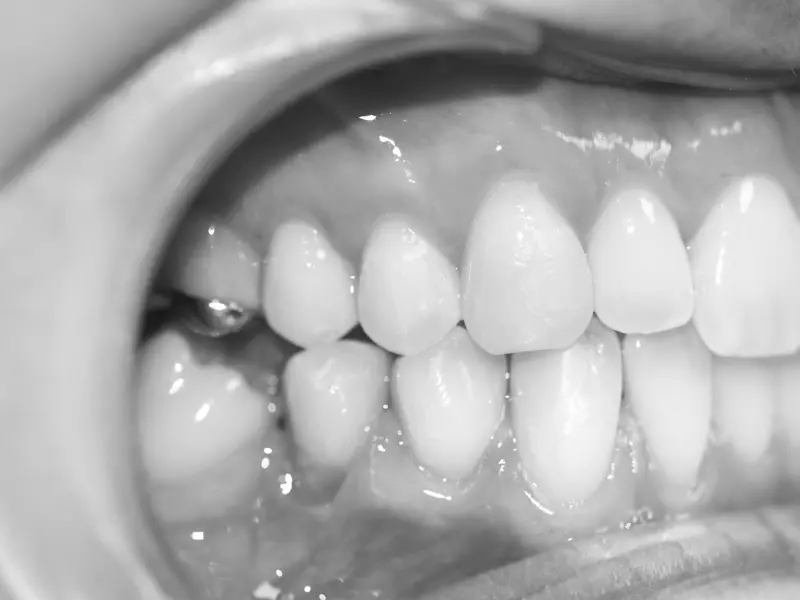

Okres noworodkowy (pierwsze dwa tygodnie życia) i niemowlęcy (od momentu odpadnięcia pępowiny do 12. miesiąca życia) powinny być objęte planowym działaniem ortodontycznym. W tych okresach rozwojowych narząd żucia jest szczególnie uzależniony od układu mięśniowego. Twarz noworodka i niemowlęcia ma od przodu kształt prawie kwadratowy. Obwód głowy noworodka jest większy od obwodu klatki piersiowej. Głowa noworodka jest cofnięta w stosunku do wystającego czoła, a w szczególności cofnięta jest żuchwa. Drobna twarz związana jest z małymi szczęką i żuchwą. Bardzo płaskie jest w tym okresie podniebienie. W okolicy przyszłych wyrostków zębodołowych znajdują się wały dziąsłowe, które mają kształt półkolisty. Na przekroju wału widać, że górny stanowi płaską nieco pochylą płaszczyznę, natomiast dolny ma kształt stożka o łagodnym spłaszczonym wierzchołku. Do okresu ząbkowania wały dziąsłowe są granicą pomiędzy przedsionkiem jamy ustnej a jamą ustną właściwą. Pomiędzy wałami znajduje się tzw. szpara owalna, która umożliwia znaczny zasięg ruchów żuchwy ku przodowi oraz sprawne ssanie pokarmu z piersi matki. Wpływa ona korzystnie na doprzedni wzrost żuchwy i rokuje prawidłowy rozwój. Wały dziąsłowe są elementem anatomicznym ustępującym w miarę wyrzynania się zębów mlecznych i kształtowania się wyrostków zębodołowych. Już około 4. miesiąca wał dolny przesuwa się ku przodowi, a około 5.–6. miesiąca zaczynają wyrzynać się zęby mleczne. Zęby sieczne podczas zwarcia żuchwy ze szczęką ustawiają się ku tyłowi od siecznych górnych, po całkowitym wyrznięciu ich zachodzenie bywa głębokie. Czynności fizjologicznego tego okresu rozwojowego to ssanie, połykanie i krzyk.